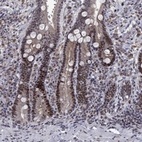

Immunohistochemical staining of human duodenum shows moderate nuclear positivity in glandular cells.